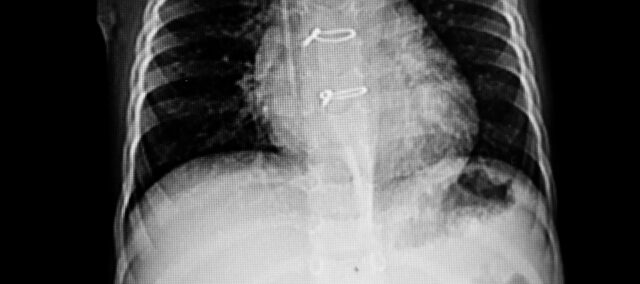

主要アウトカムは、超音波を用いて測定された胸骨分離であった。 胸骨の2つの半分の間の距離を数値化し、最大の分離点をマークした。 副次的転帰として、胸骨の完全性をグレード0(臨床的に安定した胸骨)からグレード3(大幅な移動または分離)まで評価する胸骨不安定性尺度が用いられた。 測定はベースライン(術後7日目)と4週目に行われた。

超音波検査で急性胸骨不安定症が確認された36名の女性を対象とした。 ベースラインの特徴から、2つのグループが同程度であることがわかった。 ベースラインの胸骨間隔は0.23cmであった。

主要評価項目である4週目の胸骨分離は、実験群で0.13cm、対照群で0.22cmであった。 この結果、群間差は-0.09cm(95%信頼区間0.07~0.11)となり、介入群では胸骨切開後に体幹を安定させるエクササイズを行った方が有利であった。